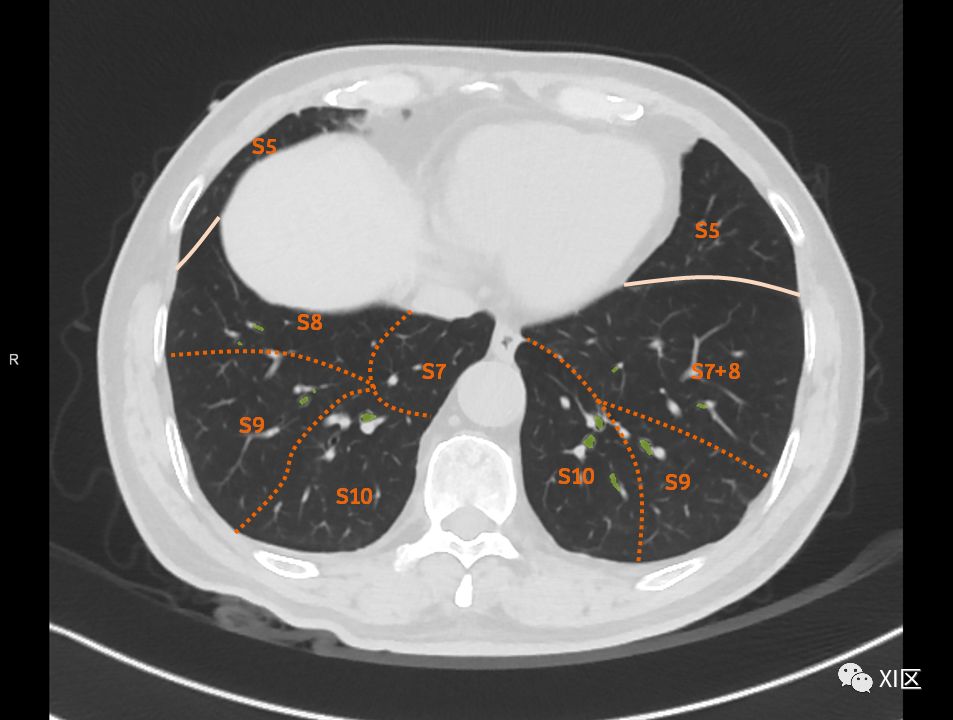

在进行肺的分段时,可以上下观察浏览,沿着相应气管的走形可以更容易准确地进行分段。

肺的断层分段示意图